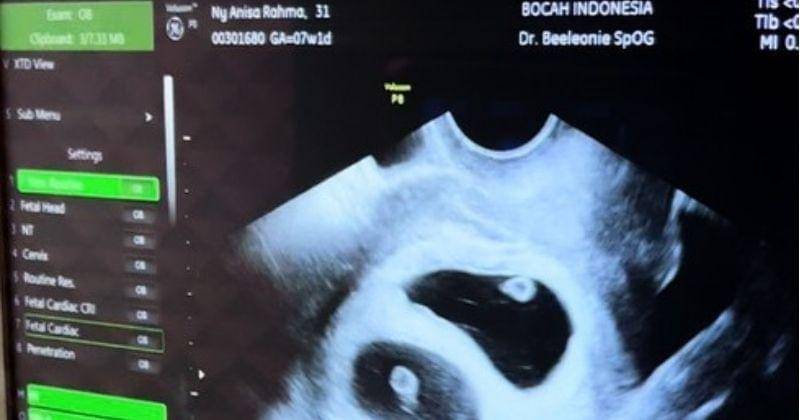

Informasi ini awalnya diunggah oleh Anisa melalui unggahan foto saat ia dan suaminya memamerkan hasil ultrasound pemeriksaan kehamilan.

Pada Selasa, 17 Mei 2022, Anisa pun membagikan kabar gembira yang sudah lama dinanti-nantikan banyak warganet melalui akun @anisarahma_12. Ia dan suaminya kompak mengumumkan kabar gembira mengenai kehamilan pertama yang mereka dapatkan dengan program bayi tabung.

Pada unggahan itu terlihat Anisa dan Anandito, serta beberapa dokter berpose sambil memamerkan hasil ultrasound milik Anisa.

5. Anisa dan Anandito Dwis mendapatkan bayi kembar

Salah satu hal yang membuat pasangan ini merasa begitu bersyukur dan tidak percaya adalah fakta bahwa Anisa mengandung anak kembar.

"Sayanggg @anisarahma_12 bener kan ini kita dikasih bayi kembar? Masih ga nyangka Ya Allah langsung duaaa.. MasyaAllah Tabarakallah. Sosok istri luar biasa, yang kuat @anisarahma_12 sehat selalu ya sayang. Semoga Allah jaga kamu dan bayi kembar kita??," ungkapnya penuh haru.